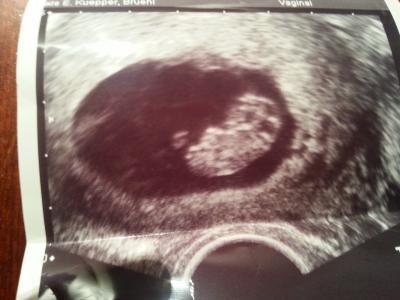

Soooo bin wieder da und wurde nach vorne gestuft bin in 2 tagen schon in der 10ssw :)) ET ist jetzt der 11.03 es ist alles super und hab auch meinen Mutterpass bekommen, am 28 hab ich schon meinen nächsten Termin. Also alles guuuuut :)) noch foto :)

Bild zu Wieder da vom FA - Forum für März - Mamis